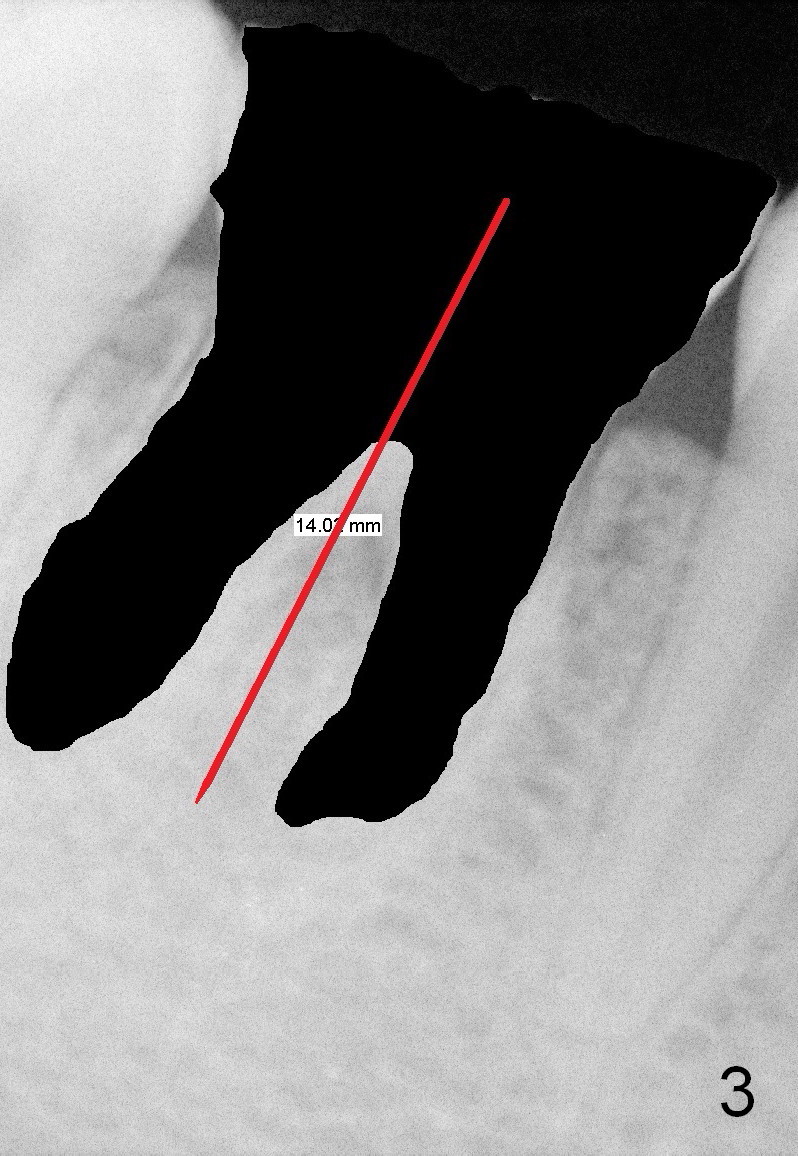

The bone height of the lower right 1st molar of a 24-year-old lady is sufficient (Fig.1). There is nearly 8 mm between the apices of the 1st lower molar and the Inferior Alveolar Nerve (Fig.2). Approximately 4-5 mm new bone can be gained for an immediate implant. Our plan is to use a relatively long and narrow bone-level implant (5.3x14 mm). Too large implant (6-8 mm) may break off the thin lateral septal wall and slide into the socket. The drawback using the smaller implant is that more bone graft is going to be used (Fig.2 red circles; collagen plug or membrane (green squares)).

An immediate provisional will be routine fabricated to close the socket opening and keep bone graft and membrane in place. In addition, the tooth #3 has supraerupted. The occlusal surface of the tooth #30 has been trimmed substantially (Fig.1). A temporary abutment may be used.